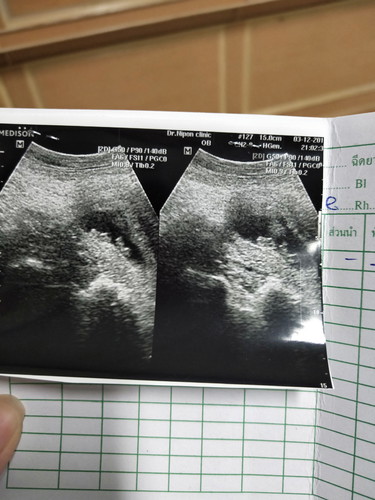

เพิ่งรู้ว่าอาการของการเป็นห่วงลูกแล้วสติแตกเป็นยังไง 3 เดือนที่ไม่เคยรู้เลยว่าในท้องแม่จะมีตัวน้อยถึงสองคน ไม่เคยแม้แต่ระวังตัวเองไม่รู้จักรักษาตัวเอง จนทำให้หนูทั้งสองคนจากแม่ไปเร็วขนาดนี้ คิดถึงนะ ????แฝดน้อยของแม่♥️✌️